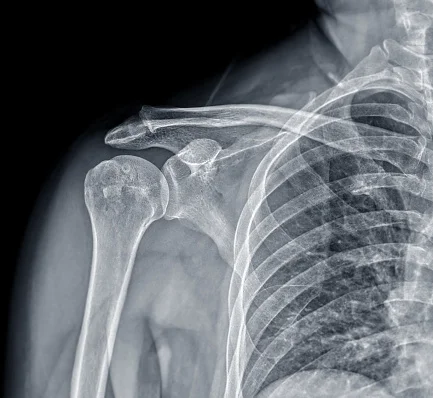

RADIOGRAFÍA DE HOMBRO

La radiografía de hombro es un examen de diagnóstico por imagen que utiliza rayos X para generar una representación detallada de la estructura ósea del hombro, lo que permite visualizar las articulaciones, huesos circundantes y posibles alteraciones en la zona.

La radiografía de hombro es un procedimiento que permite detectar y evaluar diversas afecciones, como fracturas, luxaciones, artritis, así como diversos trastornos musculares u óseos.

La radiografía de hombro es un procedimiento médico que se utiliza para obtener imágenes detalladas de la estructura ósea del hombro. Para lograr esto se emplea una máquina de rayos X que emite un haz de radiación que atraviesa el hombro del paciente y, al interactuar con los tejidos, se absorbe de manera diferente según la densidad de estos.

Por una parte, los huesos, al ser más densos, bloquean una mayor cantidad de radiación y aparecen en blanco en la imagen, mientras que los tejidos blandos permiten el paso de los rayos, mostrando tonalidades más oscuras.

La radiografía de hombro es una herramienta crucial para evaluar el estado general de la articulación en términos óseos. Permite descartar la presencia de depósitos de calcio, característicos en condiciones como la tendinitis calcificante del hombro. Del mismo modo, a través de este examen, se pueden detectar alteraciones estructurales que afectan la movilidad y funcionalidad del hombro.

Además, este tipo de radiografía es el método inicial más común para el diagnóstico de enfermedades degenerativas, como la artrosis del hombro, y resulta clave para evaluar las secuelas derivadas de fracturas previas. Al proporcionar imágenes precisas de los huesos y las articulaciones, este examen facilita a los médicos establecer un diagnóstico certero y planificar un tratamiento adecuado según la naturaleza de la patología.